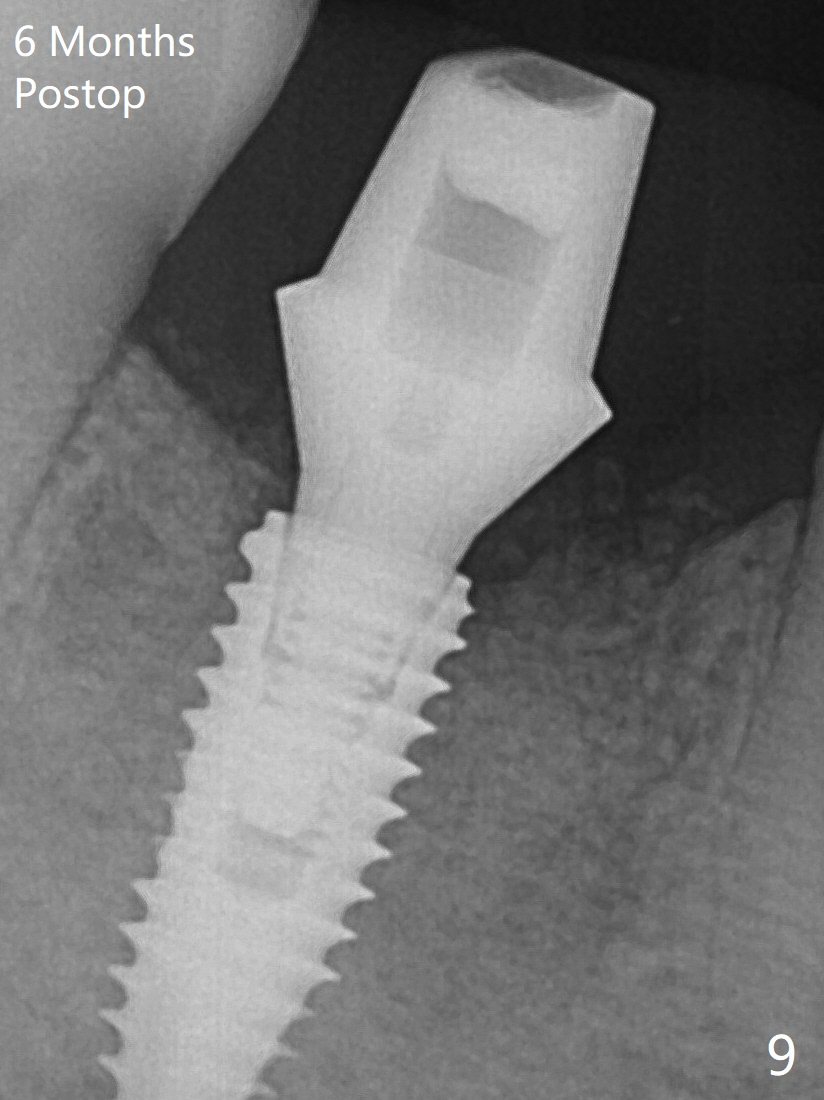

When a definitive implant (Fig.4: 4.5x11.5 mm( *: bone graft)) is placed with primary stability, there is an apical space (Fig.5 white double arrows). There is moderate postop pain. A shorter implant (10 mm) should be tried when the bone is dense. It will be associated with less pain. The fistula disappears 7 days postop (Fig.6). Although the patient appreciates that the pain is gone, there is atrophy mesiobuccally 2 months postop (Fig.7 *). The implant seems to be have been placed too buccally (Fig.8). With loss of the buccal plate, the implant should be placed away from it to prevent periimplantitis. The abutment is changed from 6.5x4(4) to 6.5x5.5 (3) mm with fabrication of a new provisional. The buccal margin is still supragingival 6 months postop and prep lower before impression (to reduce food impaction). The mesial and distal sockets appear to have healed (Fig.9). The bone density around the implant increases 11 months post cementation (Fig.12).